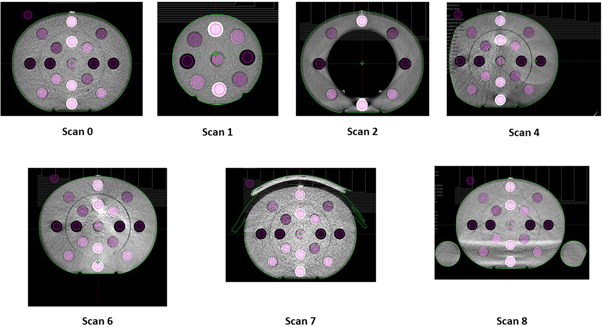

In this study, the CT-PD curve was established with the phantom centred in the FOV. In clinical applications, various setups could lead to different scatter conditions that could change the CT-PD curve. Therefore, additional tests were performed to quantify the influence of different scatter conditions on the CT-PD curve, the details of which are listed in table 1.

Table 1. Setups of additional scans quantifying the effect of scatter conditions on the CT-PD curve.

| Scan ID | Inner/outer disk | Offset distance (cm) | Offset direction | Comment |

|---|---|---|---|---|

| 0 | Both | N/A | N/A | Reference scan for 125 kV and 140 kV |

| 1 | Inner Disk Only | N/A | N/A | Reference scan for 100 kV |

| 2 | Outer Disk Only | N/A | N/A | |

| 3 | Both | 5 | Right | Not shown in figure 1 |

| 4 | Both | 10 | Right | |

| 5 | Both | 5 | Anterior | Not shown in figure 1 |

| 6 | Both | 10 | Anterior | |

| 7 | Both | N/A | N/A | A piece of 3 cm bolus is added to the anterior of the phantom |

| 8 | Both | N/A | N/A | Two bottles of water are placed adjacent to the phantom |

Raw data from each scan scenario were uploaded onto the VRP and reconstructed using the pre-clinical AcurosXB iCBCT algorithm. The reconstructed scans were subsequently imported into the Eclipse TPS to read the average HU as well as the standard deviation. The resultant HU reading of each insert was then compared to the value used by the CT-PD curve (reference scan).

Figure 1. CT-ED phantom setups to simulate different scatter conditions.

For 100 kV, not only was the HU deviation between the reference scan and other scans substantial, but the standard deviation of most scatter conditions was out of tolerance, rendering them unsuitable for dose calculations. This is because the 100 kV Head protocol is designed specifically for the H&N configuration, the typical width and length of which is approximately 15 cm and 18 cm, respectively. Therefore, when only the inner disk of the CIRS CTED phantom was scanned, both the reproducibility and the SNR of the scan were acceptable. In contrast, for the other scans where the geometry of the scanned material was larger, both the HU difference and the standard deviation were out of tolerance (i.e., >50 HU in the adipose—liver range or >100 HU in other materials). An example of Scan 4 acquired with the 100 kV Head protocol on HAL1 is shown in figure 5, which illustrates both the HU deviation between the inner and the outer disks as well as the increased noise.

Standard image High-resolution imageHU response results for the 125 kV and 140 kV protocols were similar across the scan variants. Table 5 shows that the standard deviations of both tube voltages were within the tolerance across the two linacs, indicating that the SNRs of both protocols were acceptable. This can also be seen from figure 6, which, compared to figure 5, shows significantly higher SNR under the same scatter condition.

Figure 6. CBCT image of the CIRS CTED phantom acquired with the 125 kV Pelvis protocol.

Standard image High-resolution imageTable 5 shows that high- and low-density objects appeared to be the most affected by changes in scatter conditions. The effect was most predominant when the edge of the phantom was no longer fully captured within the FOV. The issue of image truncation artefacts and HU performance in iCBCT has been addressed in the literature [23, 24]. The results in this study are consistent with those reported by Jarema et al that characterized the previous version of CBCT algorithms on Halcyon linacs [7]. As none of the incorporated algorithm additions provided in the pre-clinical algorithm addressed this data sufficiency problem, these results were in line with expectation. The impact of axial truncation resulted in calculation inaccuracy risks where small portions of the patient contour might be truncated. It should be noted that in this study, the soft-tissue inserts were placed in diagonal positions of the CIRS CTED phantom such that lateral and vertical offsets would pose similar effects on their HU variation. For both linacs, the HU deviations of both material ranges were out of tolerance when the phantom was offset by 10 cm, which indicated that under the AcurosXB iCBCT reconstruction algorithm, if the object was offset by a significant distance, the HU stability of the reconstructed images would likely collapse due to truncation artefacts, making it unsuitable for dose calculations.

Although showing a similar trend, the two Halcyon linacs behaved slightly differently under different scatter conditions. At both 125 kV and 140 kV, the HU deviation of Scan 1 acquired on HAL2 was out of tolerance but that of HAL1 was within. To ensure maximum accuracy, if the result of a linac under a certain scatter condition was out of tolerance, the clinical use of scans under the same condition was prohibited on both linacs such that instructions would remain consistent across departments.

Jarema et al reported that the existing Halcyon CBCT protocol could not be used for dose calculations in geometries with large cavities (e.g., breast/thorax patients where the lungs are included in the scan) [7] because of their significant impact on the CT-ED/PD curve. However, when the pre-clinical AcurosXB iCBCT algorithm was used, minimal HU variation was seen in Scan 2, where the inner disk of the phantom was removed to simulate breast/thorax patients. This is a major improvement of the new algorithm, which can now accurately predict the density of air cavities within the body, thereby allowing dose calculations on the CBCT images of breast/thorax patients.

From table 7, it can be seen that the 100 kV energy is only suitable for scanning small geometries such as the H&N, whereas scanning large objects will result in significant HU differences from the established CT-PD curve, as well as substantial noise that will contribute to calculation inaccuracy. In contrast, 125 kV and 140 kV are not suitable for scanning objects with a size smaller than or equivalent to that of the H&N. However, when used to scan large objects analogous to human body, their performance is acceptable in most scatter conditions. The only exceptions are Scans 4 and 6, where the phantom was offset either laterally and vertically by 10 cm, and Scan 8, where two bottles of water were added next to the phantom to simulate patient arms. Therefore, when intending to use 125 kV and 140 kV images reconstructed with the AcurosXB iCBCT algorithm for dose calculations, users should aim to reduce patient offset as well as ensuring that the patient's arms are placed out of the scan range to maximize dose calculation accuracy.